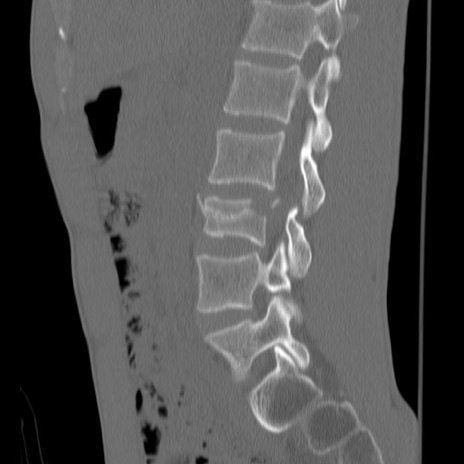

症例3 腰椎CT(矢状断像)

腰椎CT

異常所見と診断は?